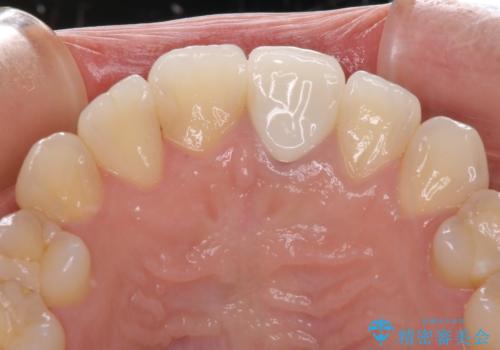

ワイヤー矯正により矯正治療を行った後に、前歯の補綴治療を行うこととしました。

変色してしまった前歯は、反対側の歯と比べて歯肉が覆い被さっていたため、骨整形を含めた歯周外科処置を行い、歯肉ラインを整えることとしました。

インビザラインでの矯正治療も十分に対応可能でしたが、自己管理の煩わしさから、ワイヤー矯正を行うこととしました。

歯周外科処置を行うかどうかは非常に悩んでいらっしゃいましたが、範囲がそれほど広くないため術後の痛みも強くないだろうということで、処置を行うこととなりました。